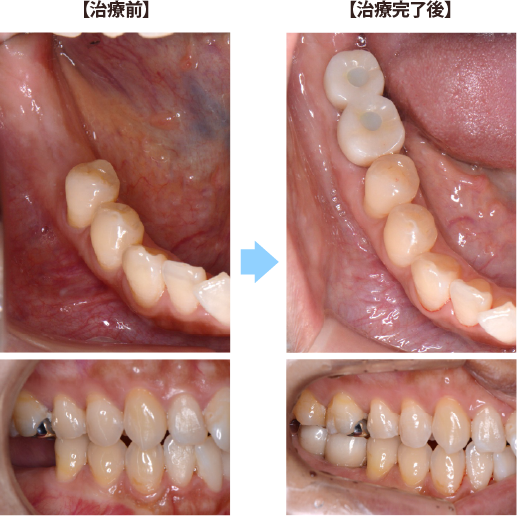

右下奥歯2本をインプラントによって再建した症例

| 治療期間 : | 2ヶ月半 |

| メリット : | 入れ歯に比べて、頑丈な強い歯を再建することができる。 天然歯と同様の咀嚼能力が回復する。(入れ歯は天然歯の20%程度の咀嚼能力) 長持ちし、他の残存歯における負担も減らすことで、残存歯本来の寿命を全うできることが多い。 虫歯にならない。 |

| リスク・副作用 : | 手術が必要であり、感染のリスクを伴う。 術後に一時的に腫れたり痛みが出ることがある。 治療完了までに数か月の期間を要する。 自費治療であり、保険治療より高額である。 インプラントも歯周病になることがある。 |

| 費用(自費治療分): | 合計金額 ¥858,000(税込) (右下大臼歯2歯分の費用、SLActive加算、ジルコニア冠の場合) |